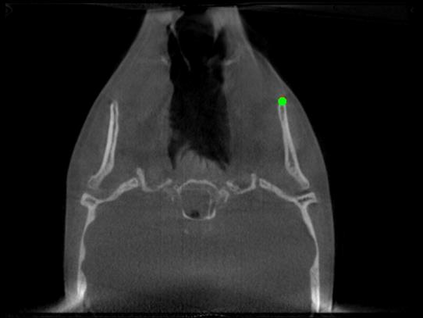

Detecting 3D landmarks on cone-beam computed tomography (CBCT) is crucial to assessing and quantifying the anatomical abnormalities in 3D cephalometric analysis. However, the current methods are time-consuming and suffer from large biases in landmark localization, leading to unreliable diagnosis results. In this work, we propose a novel Structure-Aware Long Short-Term Memory framework (SA-LSTM) for efficient and accurate 3D landmark detection. To reduce the computational burden, SA-LSTM is designed in two stages. It first locates the coarse landmarks via heatmap regression on a down-sampled CBCT volume and then progressively refines landmarks by attentive offset regression using multi-resolution cropped patches. To boost accuracy, SA-LSTM captures global-local dependence among the cropping patches via self-attention. Specifically, a novel graph attention module implicitly encodes the landmark's global structure to rationalize the predicted position. Moreover, a novel attention-gated module recursively filters irrelevant local features and maintains high-confident local predictions for aggregating the final result. Experiments conducted on an in-house dataset and a public dataset show that our method outperforms state-of-the-art methods, achieving 1.64 mm and 2.37 mm average errors, respectively. Furthermore, our method is very efficient, taking only 0.5 seconds for inferring the whole CBCT volume of resolution 768$\times$768$\times$576.